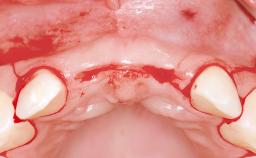

This 20-year-old woman was referred to our department in July 2006. Four months earlier, she had experienced dental trauma to the anterior maxilla when traveling in South America. The emergency treatment included emergency root canal treatment of teeth 12 and 11. Tooth 21 was also subjected to endodontic treatment later. At the initial examination, the patient was not in pain but reported increased mobility of tooth 12. The clinical examination revealed a high smile line, medium thickness of the soft tissue, and rectangular tooth forms. Discoloration of tooth 12 was evident. The periapical radiograph provided by the referring dentist indicated a fracture line at both teeth 12 and 11. A cone-beam computed tomography (CBCT) scan confirmed these fractures. No pathology was found to be associated with tooth 21.

Soft Tissue Anatomy Intact Defective

Bone Volume Horizontally and vertically sufficient Horizontally deficient Deficient vertically or deficient vertically AND horizontally